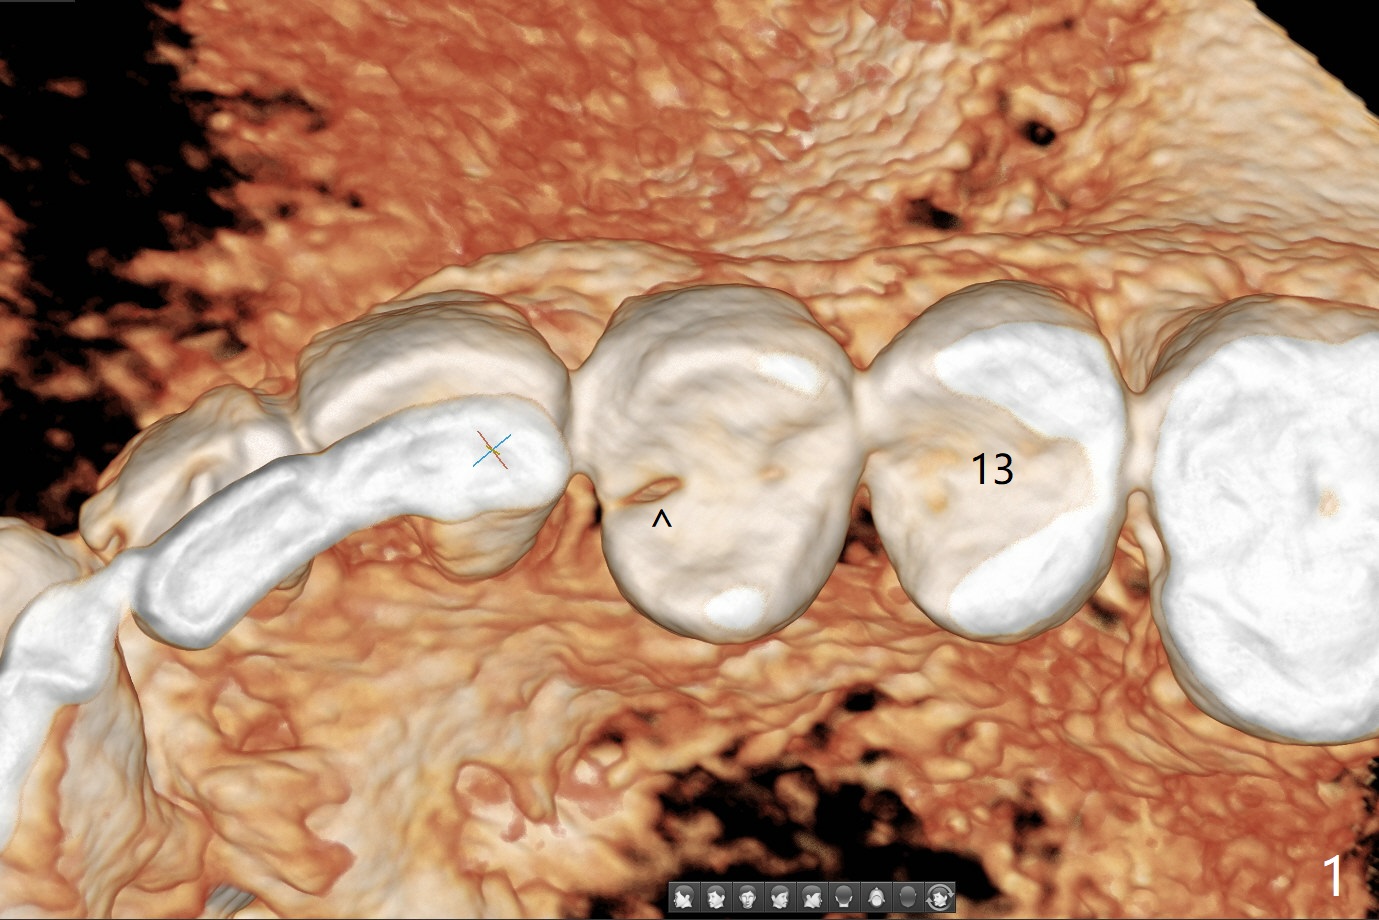

46岁男(每天两包烟,同意术前术后几天不吸烟)左上第一双尖牙折裂(图一,二(CT 3-D图)),由于折裂穿过牙髓(图三),摇动腭侧(P)断片特别痛。拔除患牙后(图四:黑色),由于窦底薄(图四:^),用锥形骨凿提升(图五(窦膜厚:黄虚线)),放置粘性骨粉后(图六),在牙槽窝腭侧骨壁中间开始钻洞(图七:红箭头),钻头尖一旦进入骨板,马上改变钻洞方向,与修复一致,然后穿过窦底(图八:绿箭头)由于窦膜已经提升,穿过窦底谅必安全。最后植入4x14或者17毫米软组织水平植体(图九),准备4毫米报废植体。Return to Protect Graft Clindamycin 前磨牙即种 Xin Wei, DDS, PhD, MS 1st edition 05/01/2021, last revision 05/03/2021